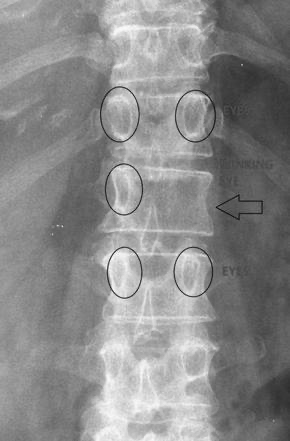

• X ray: Winking owl sign(pedicle이 erosion되어 안보이는 소견)